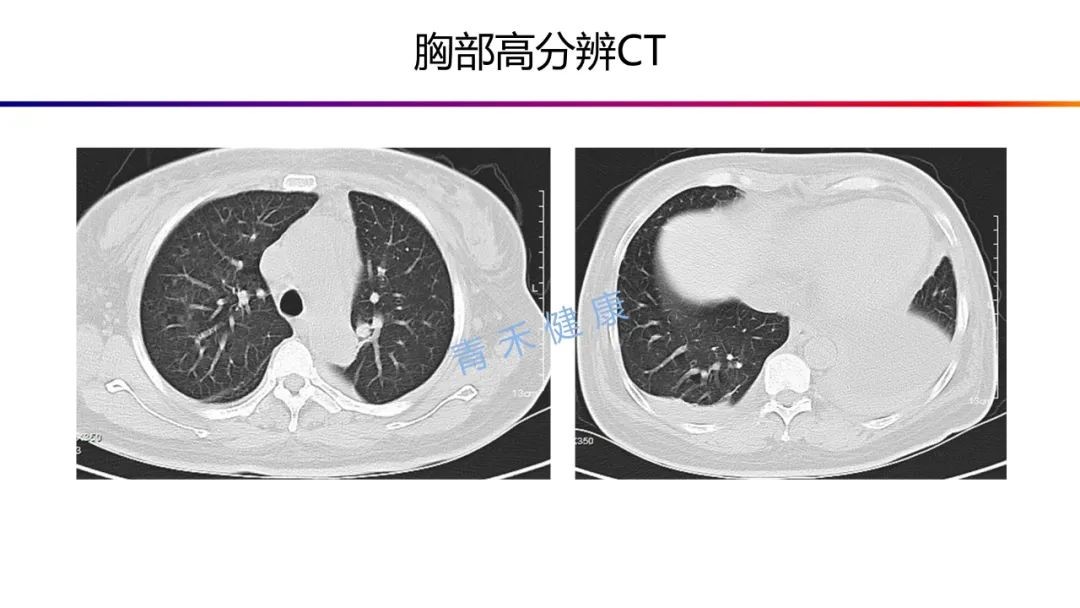

肺与纵隔-常见疾病课件.ppt

图片尺寸1152x864